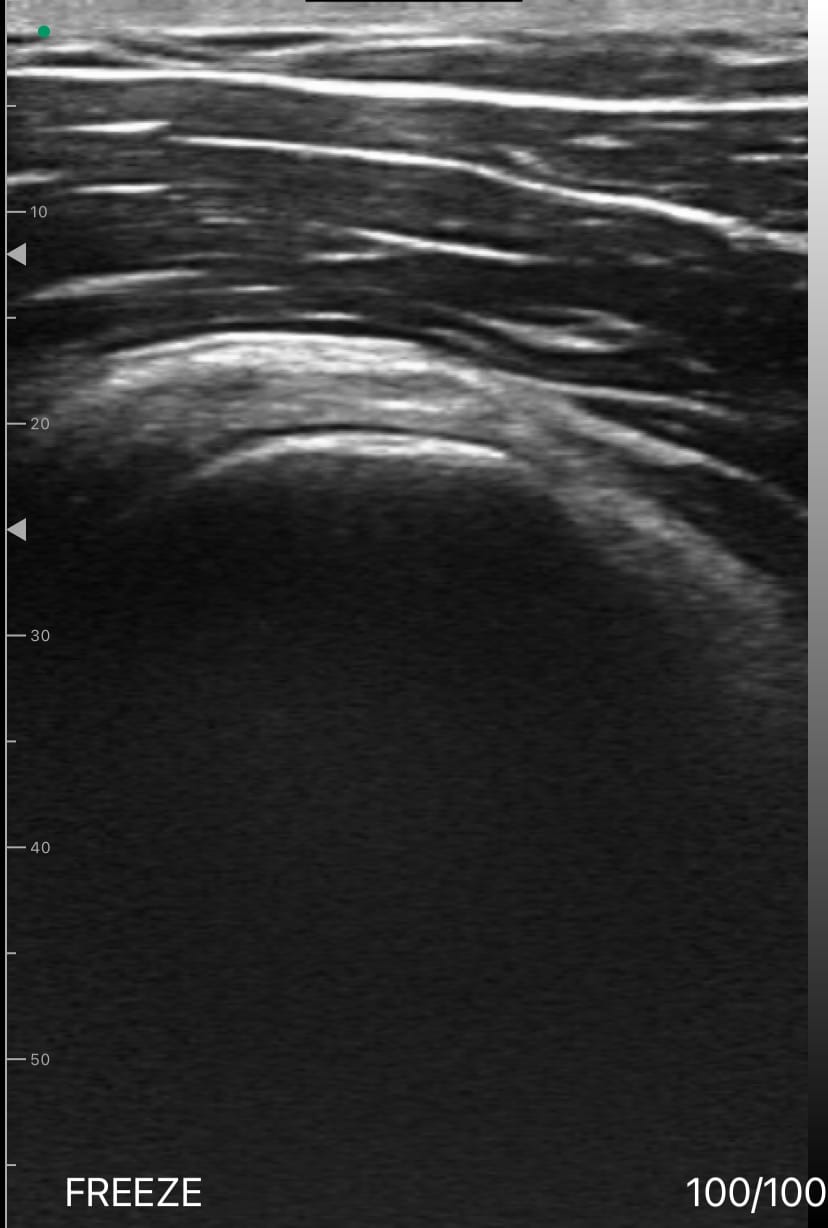

Le conflit sous-acromial

Sous-acromial